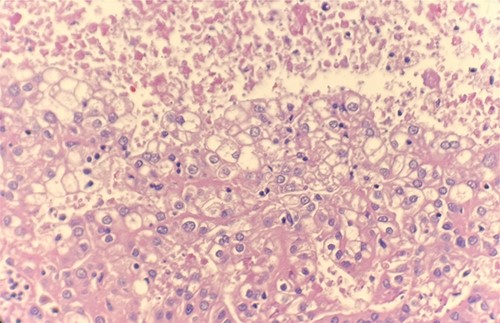

Microscopic examination revealed that clear cell RCC (Fig. 1), papillary RCC type 1 (Fig. 2), and papillary RCC type 2 (Fig. 3) were present in the right kidney, and papillary RCC type 2 was present in both kidneys. Immunostaining showed that tumor cells were positive for alpha-methyacyl-CoA racemase (Fig. 4), CD10, CK7, and vimentin, and negative for CD117.

Microscopic examination reveals small cuboidal cells arranged in a single layer on papillary cores. HE stain 40x.